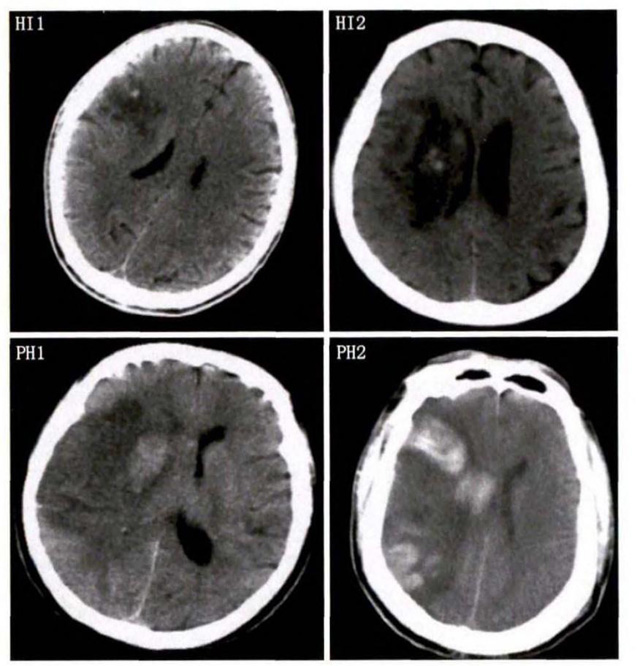

中、老年病患,有動脈粥樣硬化及高血壓病等腦卒中的危險因素,發(fā)病結(jié)合神經(jīng)系統(tǒng)癥狀和體征,應(yīng)當(dāng)考慮急性腦梗死的可能。再經(jīng)腦CT/MRI發(fā)現(xiàn)梗死灶,或排除腦出血、炎癥性疾病等,診斷即可確定。腦梗死有時頗似小量腦出血的臨床表現(xiàn)。腦栓塞在任何年齡都可以有發(fā)病的風(fēng)險,可以在幾秒到幾分鐘達到頂峰。會有偏癱不能說話等局部神經(jīng)功能損壞。栓子來源很種,可能是冠心病、心肌梗塞、心內(nèi)膜炎等。合并心房纖顫,結(jié)合其他臟器官的支持診斷,CT跟磁共振都可以檢查確定栓塞位置數(shù)量還有是不是有伴發(fā)出血等問題??梢詭椭\斷。

中老年有高血壓糖尿病發(fā)病病史,起病神經(jīng)功能缺損癥狀,臨床表現(xiàn)為腔隙綜合征,即可初步診斷本病。如果CT或磁共振證實有與神經(jīng)功能缺失一致的腦部腔隙病灶, 符合大腦半球或腦干深部的小穿通動脈病變,即可明確診斷。少數(shù)患者隱匿起病,無明顯臨床癥狀,在影像學(xué)檢查時發(fā)現(xiàn)。